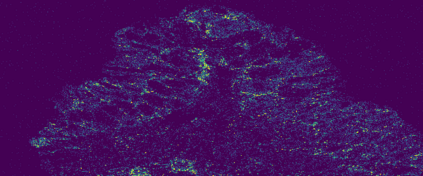

The usage of chemical imaging technologies is becoming a routine accompaniment to traditional methods in pathology. Significant technological advances have developed these next generation techniques to provide rich, spatially resolved, multidimensional chemical images. The rise of digital pathology has significantly enhanced the synergy of these imaging modalities with optical microscopy and immunohistochemistry, enhancing our understanding of the biological mechanisms and progression of diseases. Techniques such as imaging mass cytometry provide labelled multidimensional (multiplex) images of specific components used in conjunction with digital pathology techniques. These powerful techniques generate a wealth of high dimensional data that create significant challenges in data analysis. Unsupervised methods such as clustering are an attractive way to analyse these data, however, they require the selection of parameters such as the number of clusters. Here we propose a methodology to estimate the number of clusters in an automatic data-driven manner using a deep sparse autoencoder to embed the data into a lower dimensional space. We compute the density of regions in the embedded space, the majority of which are empty, enabling the high density regions to be detected as outliers and provide an estimate for the number of clusters. This framework provides a fully unsupervised and data-driven method to analyse multidimensional data. In this work we demonstrate our method using 45 multiplex imaging mass cytometry datasets. Moreover, our model is trained using only one of the datasets and the learned embedding is applied to the remaining 44 images providing an efficient process for data analysis. Finally, we demonstrate the high computational efficiency of our method which is two orders of magnitude faster than estimating via computing the sum squared distances as a function of cluster number.